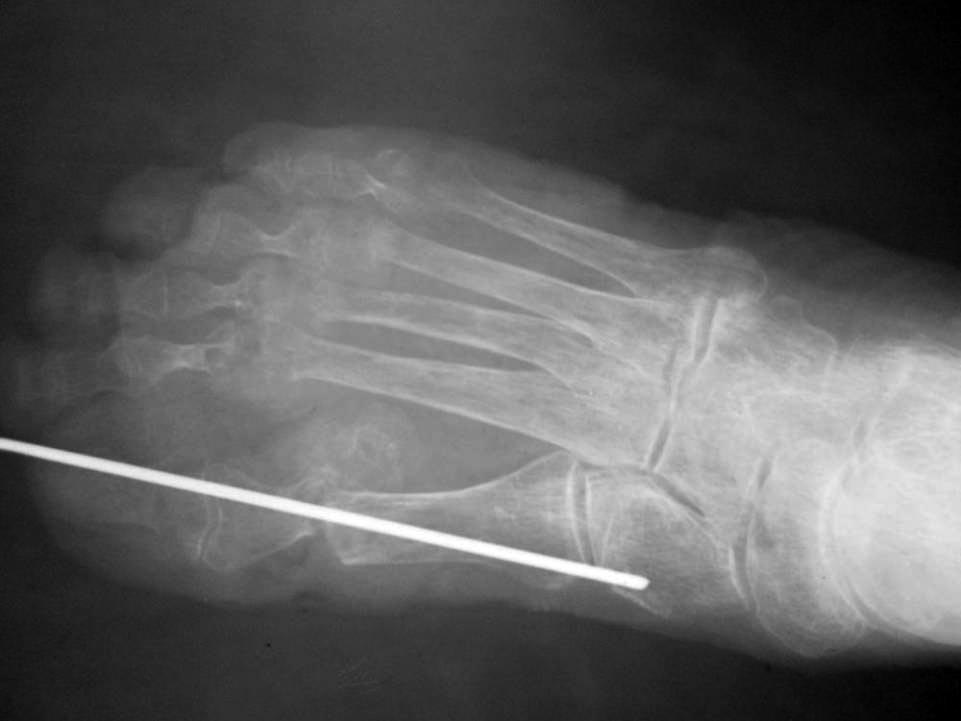

Обратилась больная 75 лет с нallux abductovalgus. начало деформации отмечает с 16 лет. лечение не проводилось.

причина обращения - появление болезненных, длительно незаживающих пролежней на подошвенной поверхности головок 1-х плюсневых костей. Уважаемые коллеги,подскажите пожалуйста план реконструктивной операции.

Случай очень сложный. И по рентгенограмме в одной проекции разобраться невозможно. Как минимум нужна еще одна проекция и фото стопы с тыльной и подошвенной стороны. Ведь по одному снимку неясно, какие пальцы лежат сверху, какие снизу, в каком состоянии сейчас пролежни. А еще лучше - компьютерная томограмма, которая позволит точно понять взаимоотношения фаланг и плюсневых костей, размеры, форму и положение сесамовидных костей.

рентген

Пациентке выполнен артродез 1-ого плюснефалангового сустава, резекции говок 2-3 плюсневых костей, субкапитальная остеотомия 4 плюсневой кости, тенотомиии разгибаталей 2-5 п. стопы. Раны зажили первичным натяжением.